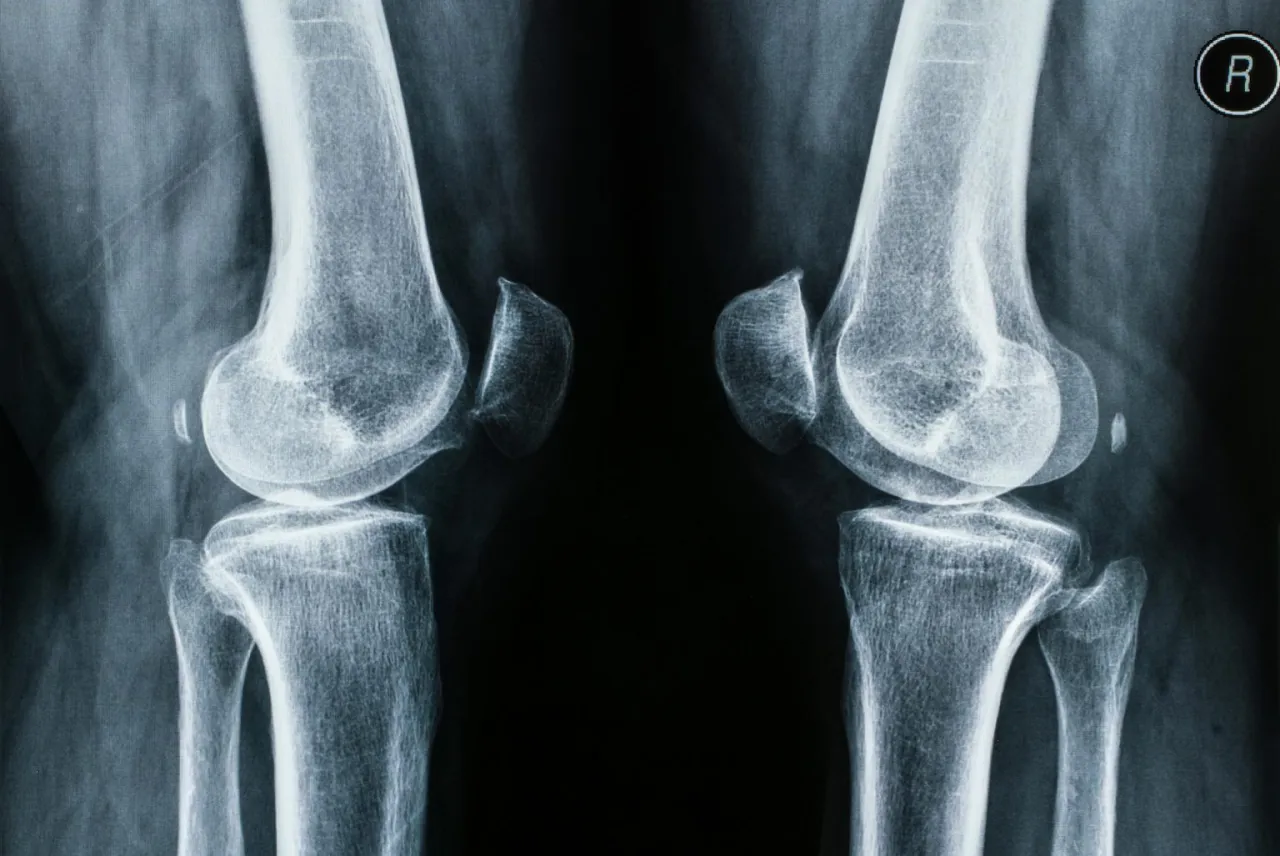

- Ortopeda-traumatolog specjalizuje się w całym narządzie ruchu: kościach, stawach, mięśniach, więzadłach i ścięgnach, w tym w leczeniu urazów takich jak złamania czy skręcenia.

- Ortopeda jest właściwym wyborem przy bólu stawów (kolana, biodra), urazach sportowych, złamaniach, skręceniach czy przewlekłym bólu kręgosłupa.

Ortopeda, a właściwie specjalista ortopedii i traumatologii narządu ruchu, to lekarz, który zajmuje się kompleksowo całym Twoim układem ruchu. Oznacza to, że jego uwaga skupia się na kościach, stawach, mięśniach, więzadłach i ścięgnach. W Polsce specjalizacja ta jest zintegrowana z traumatologią narządu ruchu, co sprawia, że każdy ortopeda jest również chirurgiem urazowym, doskonale przygotowanym do leczenia skutków wypadków i kontuzji.

Zakres działania ortopedy jest niezwykle szeroki od diagnozowania i leczenia schorzeń wrodzonych i nabytych, przez urazy sportowe i powypadkowe, po choroby zwyrodnieniowe. Ortopeda stosuje zarówno metody leczenia zachowawczego, jak i operacyjnego, zawsze dążąc do przywrócenia pełnej sprawności i komfortu życia pacjenta.

- Urazy sportowe i powypadkowe: Złamania kości, skręcenia stawów (np. kostki, kolana), zwichnięcia, uszkodzenia więzadeł (np. krzyżowych w kolanie) czy łąkotek to klasyczne przypadki wymagające interwencji ortopedy.

- Przewlekły ból stawów: Jeśli cierpisz na długotrwały ból w kolanach, biodrach, barkach czy innych stawach, który może być objawem choroby zwyrodnieniowej, ortopeda pomoże zdiagnozować przyczynę i zaplanować leczenie.